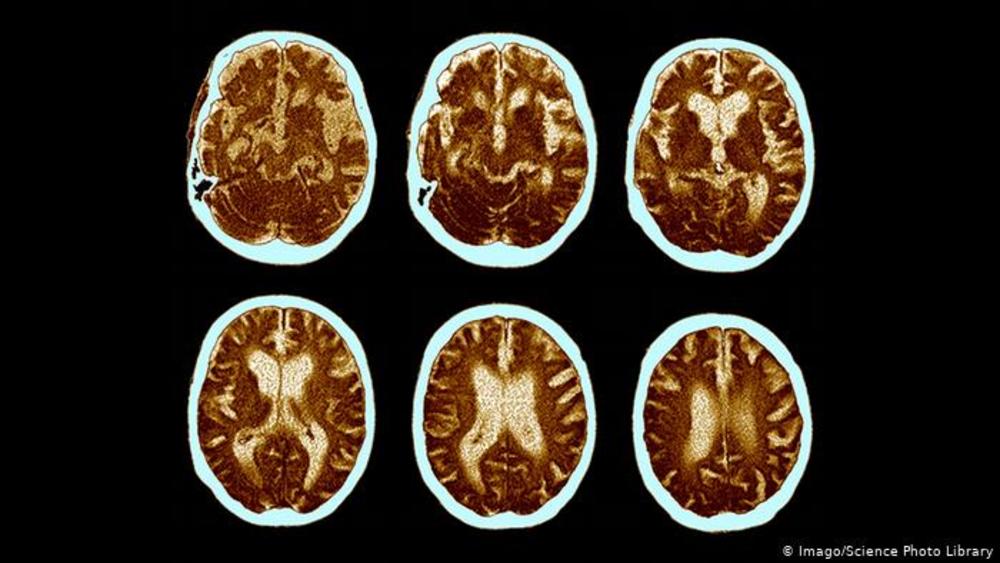

دمانس اختلال مزمن و گاه حاد در فرآیندهای روانی است که از جمله با اختلال در حافظه هم همراه است. بیماری فراموشی یا آلزایمر، شایع‌ترین نوع دمانس، یک نوع اختلال عملکرد مغزی است.

برای بیماری آلزایمر که در آن سلول‌های مغز از بین می‌روند، در حال حاضر درمانی قطعی وجود ندارد. اما در مورد تشخیص زودهنگام این بیماری در افرادی با ریسک‌پذیری بالا برای ابتلا چطور؟

به همین علت تشخیص بیماری از روی نخستین نشانه‌‌ها و زمینه‌های بروز آن برای کند کردن روند توسعه بیماری با استفاده از دارو، از اهمیت ویژه‌ای برخوردار است. یک روش برای تشخیص به موقع، ارزیابی اسکن مغزی با بهره‌گیری از هوش مصنوعی است.